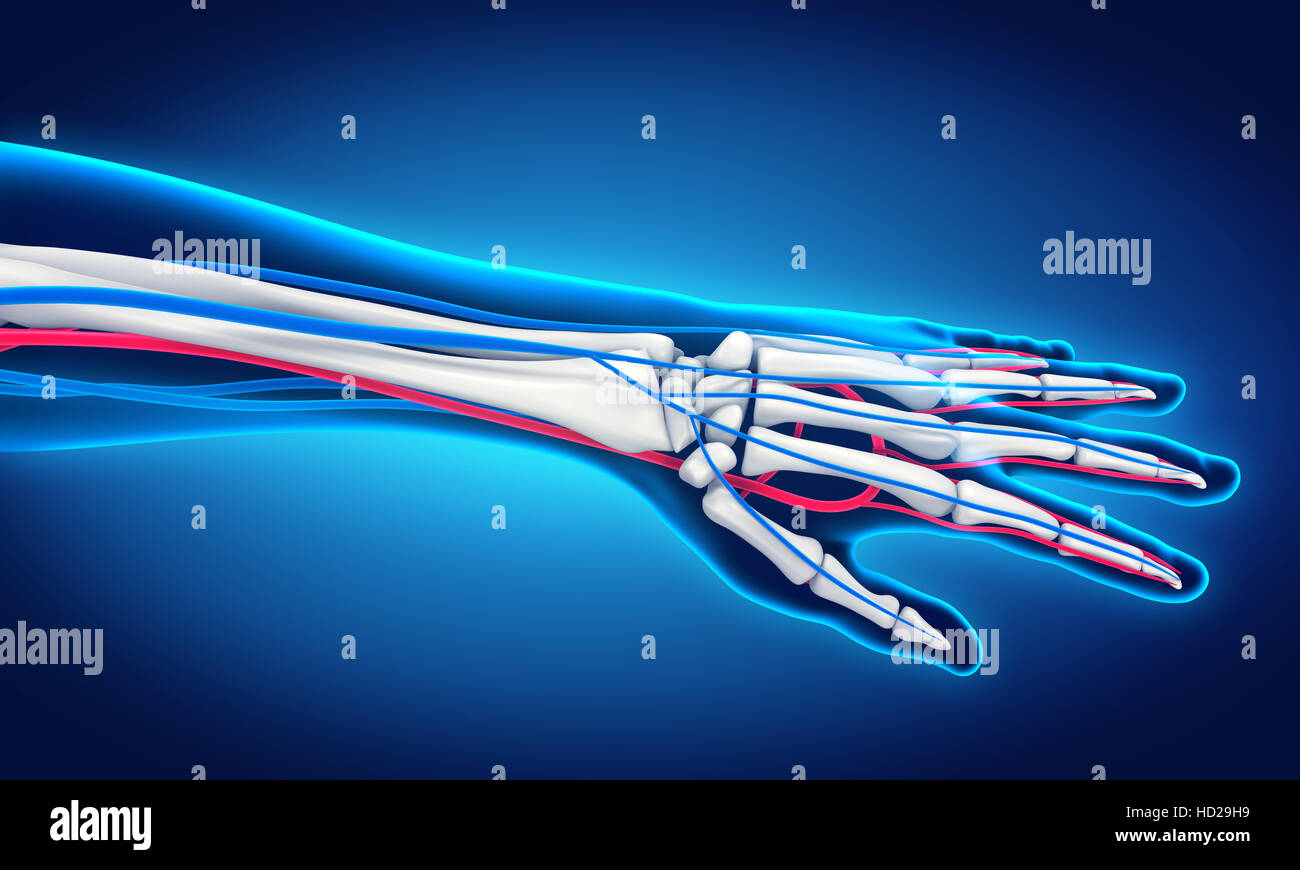

Venas de la mano. 3d fotografías e imágenes de alta resolución Alamy

Arterias y venas de la mano fotografías e imágenes de alta resolución Página 2 Alamy